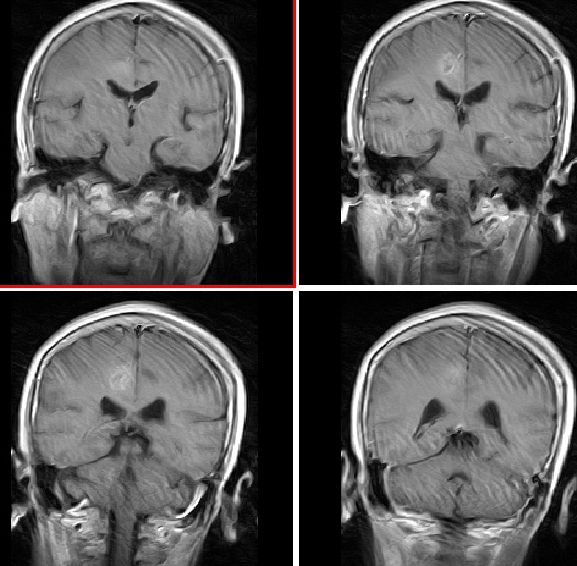

mri增强

mr表现:中央旁小叶区病灶号不均匀性稍长t1、长t2信号,病灶周边见稍短t1信号环。右侧脑室体旁见点片状等t1、稍长t2信号影。flai序列各病灶均呈高信号。增强后右侧中央旁小叶区病灶呈不均匀性强化。

右侧中央旁小叶结节样占位,边界清楚,周围未见明显水肿,t1wi呈低信号,t2wi呈高信号,增强扫描明显不均匀强化。未见流空畸形血管团及引流静脉,所以考虑海绵状血管瘤。低级别胶质瘤一般血脑屏障无破坏,强化不明显。